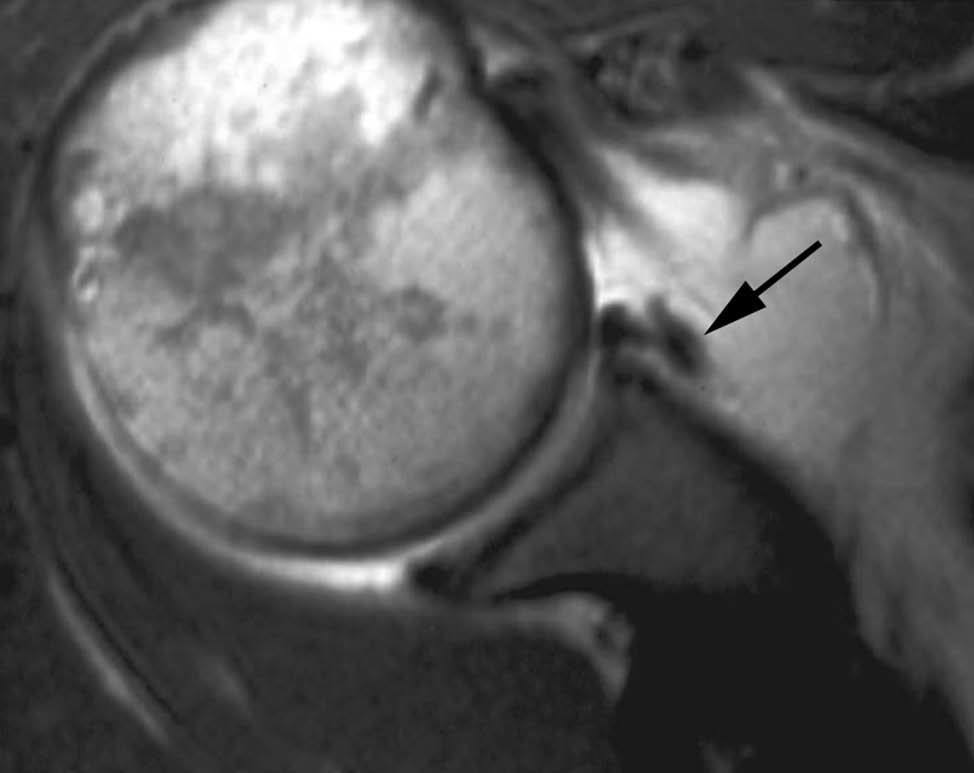

Fig. 2.--Receso sublabial. Artrorresonancia T1 coronal oblicua que muestra un receso profundo sublabial. Nótese la orientación de esta variante hacia la cabeza del paciente (flecha).

En la mayoría de los casos, el LG está firmemente adherido al margen de la glenoides. Eventualmente, existe una falta de adherencia del LG en el margen anterosuperior de la glenoides, produciéndose en la RM una falsa imagen de rotura6 (fig. 1). El espacio que se produce debido a esta falta de adherencia se llama el «foramen sublabial». Una segunda causa de error diagnóstico es el receso sublabial, que se halla en el borde superior del LG6. Esta variante de la normalidad puede confundirse con una rotura del labio superior (lesión de SLAP) (fig. 2). En términos generales, el receso sublabial se extiende hacia la dirección de la cabeza del paciente, mientras que la lesión de SLAP se extiende hacia el hombro del paciente. En algunas ocasiones, el receso sublabial se asocia a un engrosamiento del LG superior (labio meniscoide).